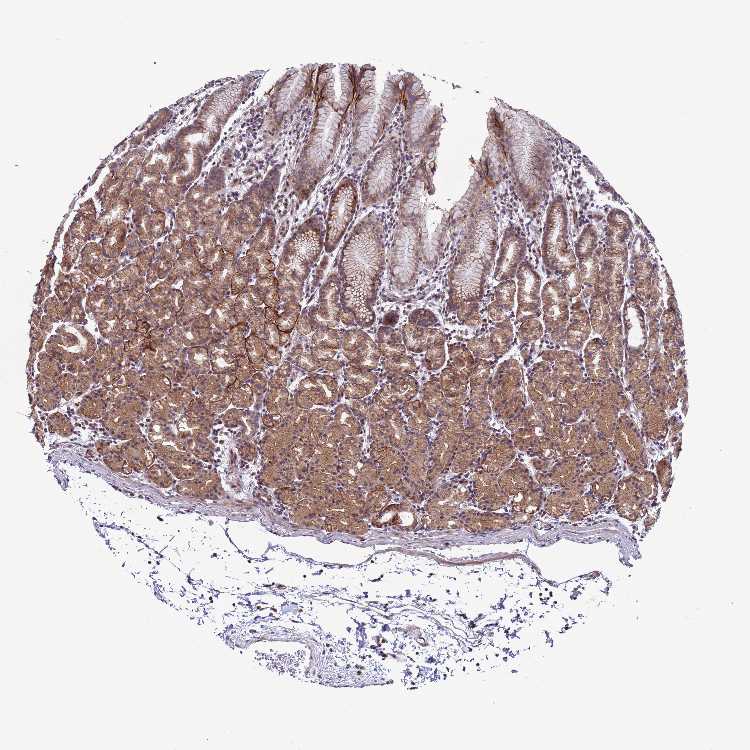

TISSUE PRIMARY DATA STOMACH Show tissue menu

STOMACH 1 - Antibody stainingi

Antibody HPA045797

Glandular cells High

STOMACH 2 - Antibody stainingi